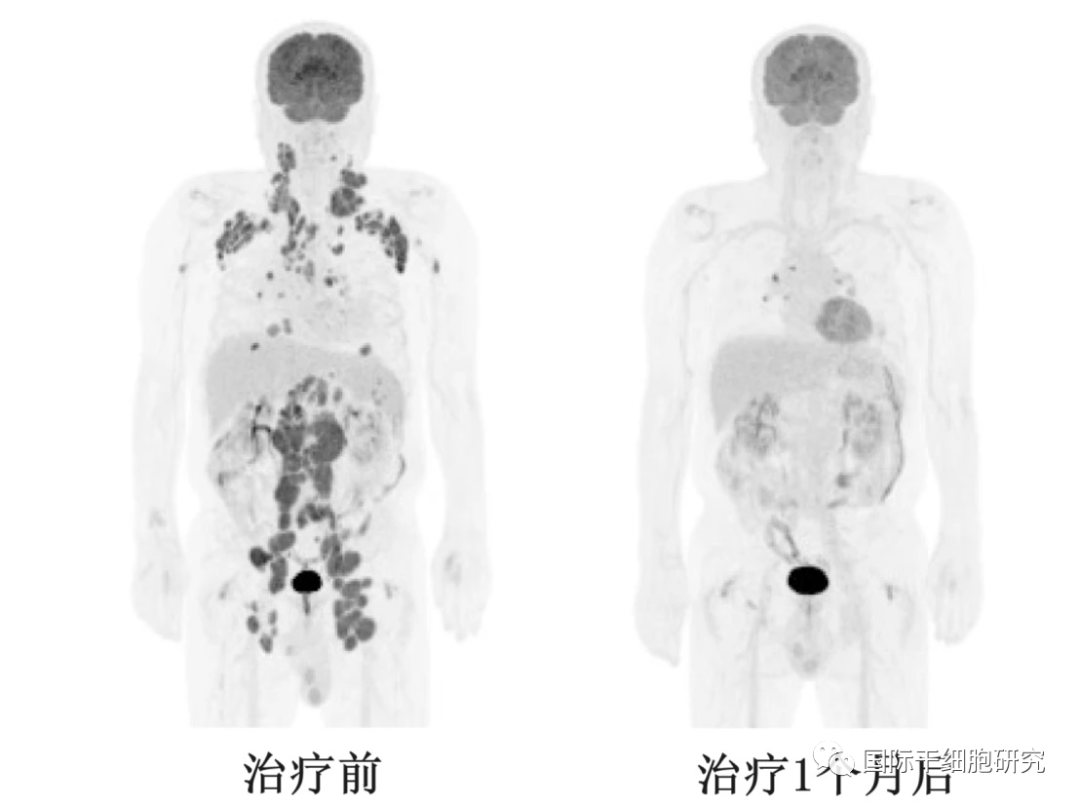

图1 AT101治疗前后PET/CT对比

注:10号患者在接受AT101治疗前、治疗1个月后的PET/CT图像,显示出完全的代谢反应。

值得注意的是,在接受活性剂量AT101(DL-2和DL-3)的患者(n=6)中,CR为100%。中位随访时间为9.3个月(1.5-16.5个月),无进展生存期(PFS)达75.0%,总生存率(OS)为82.5%。总之,在本次临床试验中,AT101的早期反应惊艳!